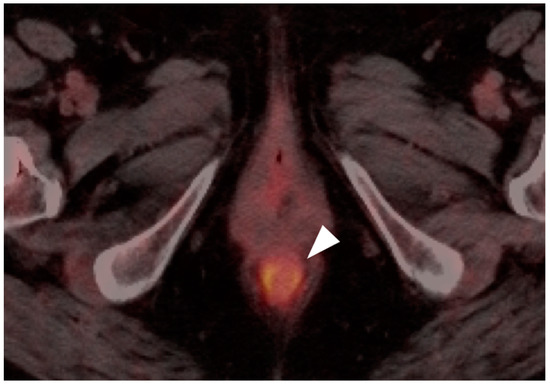

10. Anal Carcinoma